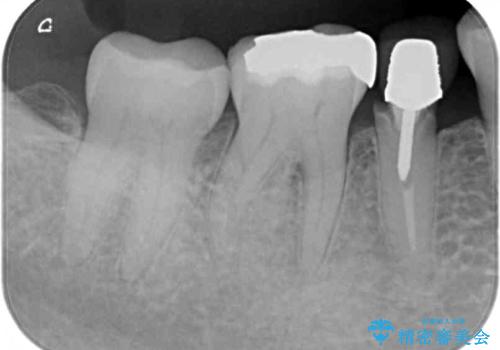

- メインテナンスの際、以前よりものが挟まることが気になっていた患者様です。

神経が取り除かれた歯であるため、虫歯で歯が失われていく際に痛みを伴わなず、気がついたら大きな穴があいていました。

虫歯を全て除去したうえで新しい土台を築製し、セラミッククラウンにより補綴治療を行うこととしました。

虫歯が歯根深くまで及んでいる場合には歯を部分矯正で引っ張り出したり、歯周外科処置が必要となったりしますが、メインテナンスでレントゲン写真を定期的に撮っていたため、幸いにも矯正や外科処置が必要となる前に補綴治療を行うことができました。